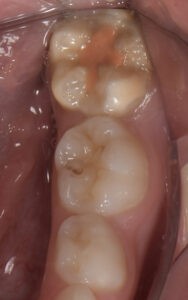

Le congrès de l’EAPD (Académie Européenne d’Odontologie Pédiatrique) a défini des critères de diagnostic en 2003. A savoir des opacités délimités, des fractures post-éruptives, des restaurations atypiques ainsi que que des extractions des molaires. (3) Le diagnostic différentiel doit surtout s’établir entre des amélogénèses imparfaites et des hypominéralisations d’origine traumatique pour les dents antérieures. Cliniquement, les dents vont présenter des colorations blanches ou brunes opaques sur une partie ou sur toute la surface de la dent (Figures 1-2-3-4).

formation dentaire pédodontie Figure 1.

MIH, état des lieux et thérapeutiques Figure 2.

Figures 1-2 : Incisives centrales atteintes de MIH

Figure 3-4 : Molaires atteintes de MIH (HSPM + MIH pour la figure 3)